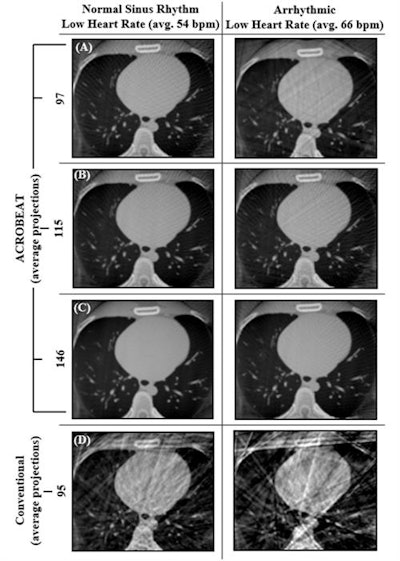

Reconstructed cardiac-gated 3D images for acquisition windows of 60% to 70% through the cardiac cycle for ACROBEAT, with an average of 97 (A), 115 (B), and 146 (C) projections; and conventional multisweep retrospective gated protocol (D) with 95 projections. Image courtesy of Reynolds et al, Phys Med Biol, 10.1088/1361-6560/ab03f4.

Reconstructed cardiac-gated 3D images for acquisition windows of 60% to 70% through the cardiac cycle for ACROBEAT, with an average of 97 (A), 115 (B), and 146 (C) projections; and conventional multisweep retrospective gated protocol (D) with 95 projections. Image courtesy of Reynolds et al, Phys Med Biol, 10.1088/1361-6560/ab03f4.Increasing the acquisition window from 60%-70% to 60%-80% resulted in fewer streak artifacts in conventional retrospectively gated images for the two regular ECG traces but not in the arrhythmic trace. Increasing the window length did not have a detrimental effect on either the C/N ratio or ERW of the ACROBEAT images. For medium and arrhythmic heart rates, the 60% to 80% window significantly reduced total scan time, although it slightly increased scan time for the low heart rate.

Cardiac images reconstructed using the conventional protocol contained streak and blurring artifacts for all three ECG traces. In all ACROBEAT simulations, these artifacts almost completely disappeared.

For all ECG traces and 10% acquisition windows, ACROBEAT increased the contrast-to-noise (C/N) ratio compared with the conventional protocol, indicating better visibility of image features. The edge response width (ERW), a measure of boundary sharpness between adjacent regions, was also lower (indicating sharper images) in ACROBEAT simulations than in equivalent conventional images.